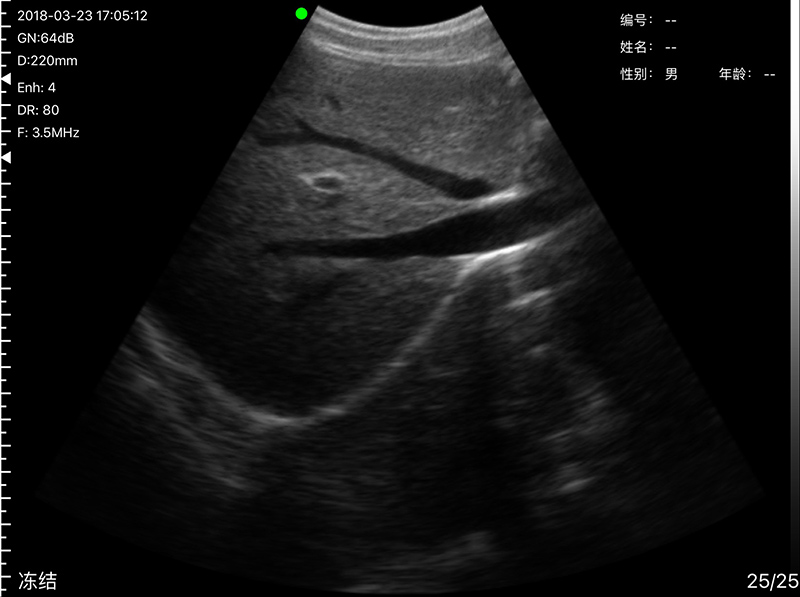

• 探头频率:凸阵3.2/5.0MHz,腔内6.0/8.0 MHz

• 扫描声头:同时具备凸阵、腔内两个声头,并可通过按键快速切换

• 扫描深度:凸阵90/160/220/305mm,腔内 30/60/90/120mm,可调

• 扫描角度和宽度:凸阵R60,腔内R13